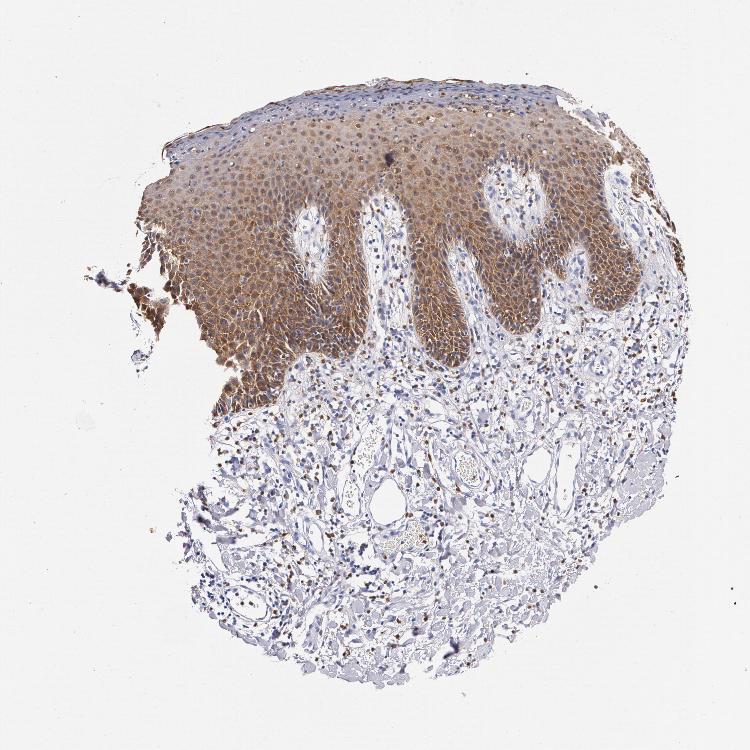

TISSUE PRIMARY DATA SKIN Show tissue menu

SKIN 1 - Antibody stainingi

Antibody staining in the annotated cell types in the current human tissue is reported as not detected, low, medium, or high, based on conventional immunohistochemistry profiling in selected tissues. This score is based on the combination of the staining intensity and fraction of stained cells.

Each image is clickable and will lead to virtual microscopy that enables deeper exploration of all samples and also displays staining intensity scores, fraction scores and subcellular localization as well as patient and tissue information for each sample.

SKIN 2 - Antibody stainingi

Antibody HPA024372Antibody CAB002791

Cells in basal layer Low-

Cells in corneal layer Medium-

Cells in granular layer High-

Cells in spinous layer High-

Endothelial cells Not detected-

Epidermal cells -High

Extracellular matrix Not detected-

Fibrohistiocytic cells High-

Langerhans cells High-

Lymphocytes Not detected-

Melanocytes Not detected-

Vascular mural cells Not detected-